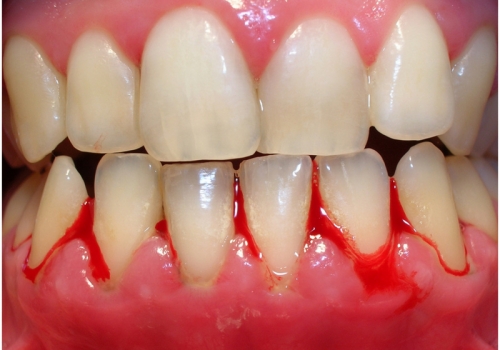

Parodontitin əsas əlamətləri bunlardır:

- Diş ətində şişkinlik və qızartı

- Diş ətində qanamağa meyllilik